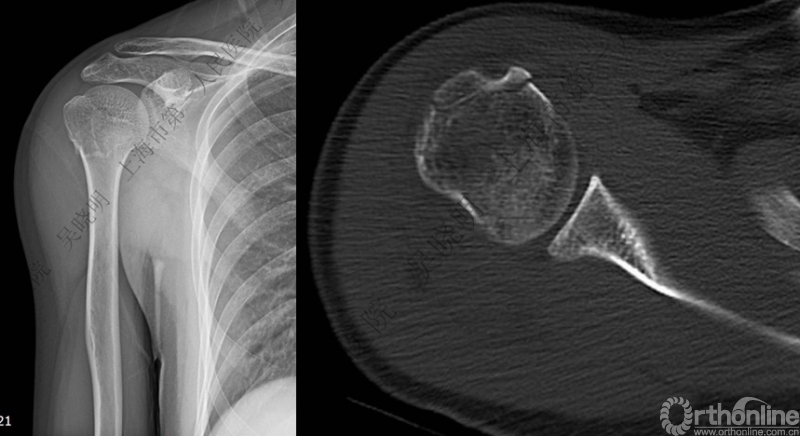

肩关节前脱位伴大结节骨折创伤机制2:肩胛盂与肱骨头撞击

老年性肩关节脱位伴大结节骨折:与肩胛盂和肱骨头撞击有关

骨折线可以延伸到肱骨头

特别警惕伴肱骨头外翻合并大结节骨折的肩关节脱位

肩关节前脱位伴大结节骨折:颈干角正常

无肱骨头外翻伴大结节骨折的老年性肩关节前脱位

Neer 分型:二部分大结节骨折脱位:手法复位